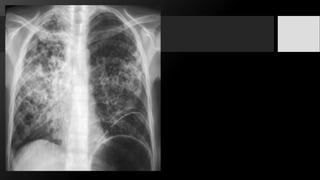

Infiltrados Pulmonares:

• Grupo de opacidades que aparecen donde normalmente existía transparencia

pulmonar. Son imágenes radiopacas que aparecen donde normalmente había imágenes

radiolúcidas.

• Los que comprometen el espacio aéreo, que son los infiltrados de tipo alveolar.

• Los que comprometen el intersticio que son los infiltrados intersticiales.

Infiltrado retículo-nodular